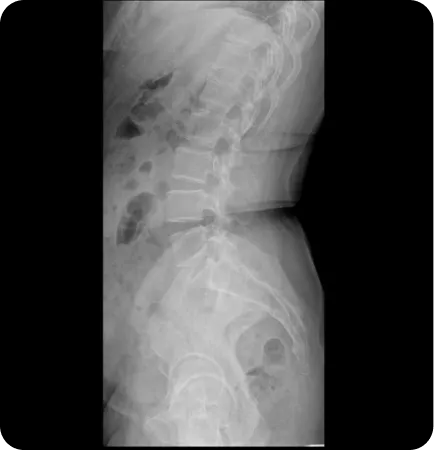

뒤로 기운 골반

(골반 후방 경사)

골반이 뒤로 기울어져 허리가 편평하며

허벅지 뒤쪽 근육이 많이 짧아진 유형

• 허벅지 뒤쪽 근육과 복근을 이완하고 허리근육과 허벅지 앞쪽 근육을 강화하는 도수치료

• 천골과 장골 변위를 교정하는 추나요법

• 요족인 경우 맞춤깔창 처방